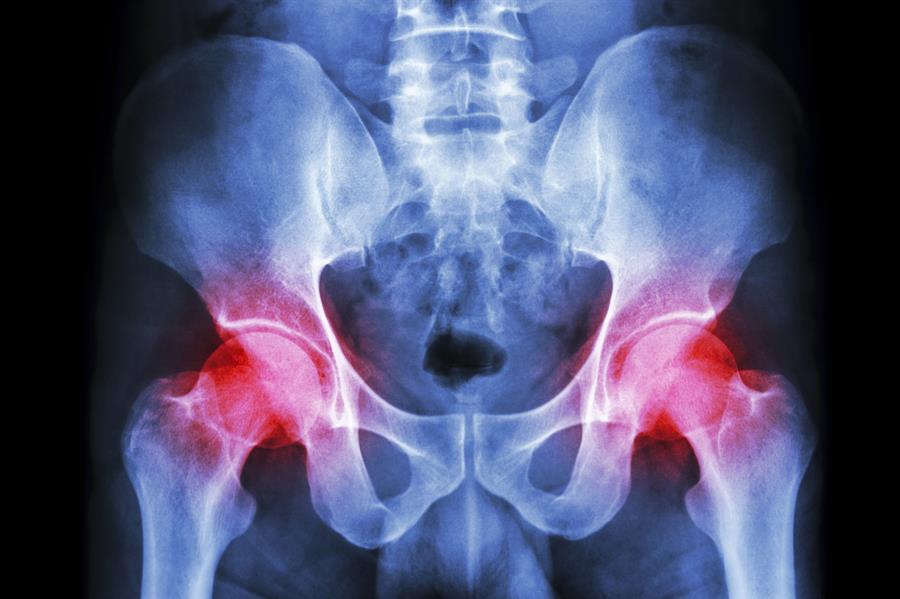

Est-il temps pour un remplacement de la hanche ?

Ne semble-t-il pas que si une chose est réparée ou remplacée, quelque chose d'autre se brise ? Les voitures, les ordinateurs, les appareils électroménagers... même nos hanches et nos genoux ! C’est parce qu’ils sont eux aussi sujets à l'« usure » au fil du temps, contribuant au développement de problèmes avec les articulations comme l’arthrose, qui provoque de la douleur, de la raideur et une diminution de la mobilité.